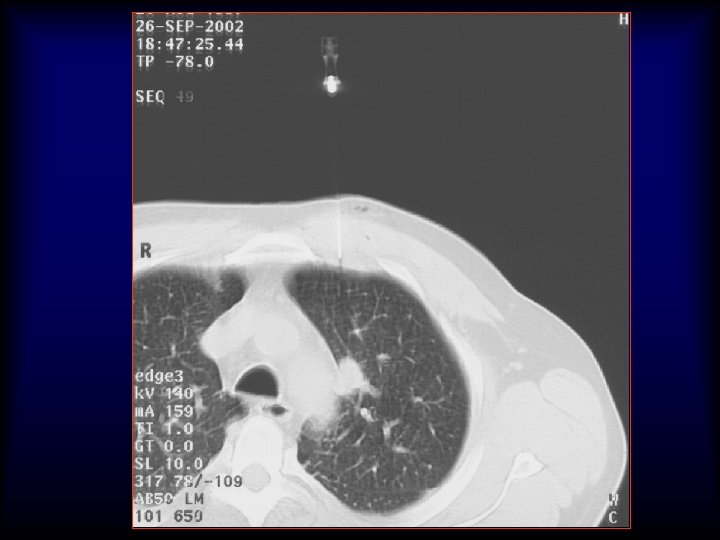

20 G/9 cm/10 T x 25 x 40 x 200 5 mm Adenocarcinoma H&E